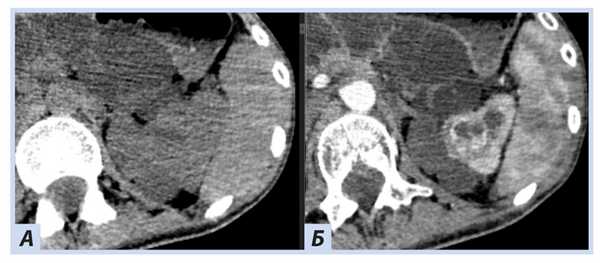

При скрининговом ультразвуковом исследовании забрюшинного пространства были выявлены изменения обеих почек, которые были интерпретированы как множественные кисты при дообследовании на КТ забрюшинного пространства: множественные кистозные образования обеих почек; в верхнем полюсе левой почки — кистозно-солидное образование, изоденсное паренхиме почки в нативную фазу (40 HU), в артериальную активно накапливающее контраст (до 100 HU), контуры его четкие неровные (рис. 5, 6).

Рис. 5. Пациентка П., 30 лет, с диагнозом «Болезнь Гиппеля−Линдау»: компьютерная томография забрюшинного пространства

Примечание. А — нативная фаза: кисты обеих почек, солидный узел в верхнем полюсе левой почки; Б — артериальная фаза: кисты обеих почек более отчетливы на фоне контрастированной почечной ткани, солидный узел в верхнем полюсе левой почки с неоднородным накоплением контраста опухолью.

Рис. 6. Пациентка П., 30 лет, с диагнозом «Болезнь Гиппеля−Линдау»: компьютерная томография забрюшинного пространства

Примечание. А — нативная фаза: кистозно-солидное образование левой почки; Б — артериальная фаза: кистозно-солидное образование левой почки с неоднородным накоплением контраста опухолью.